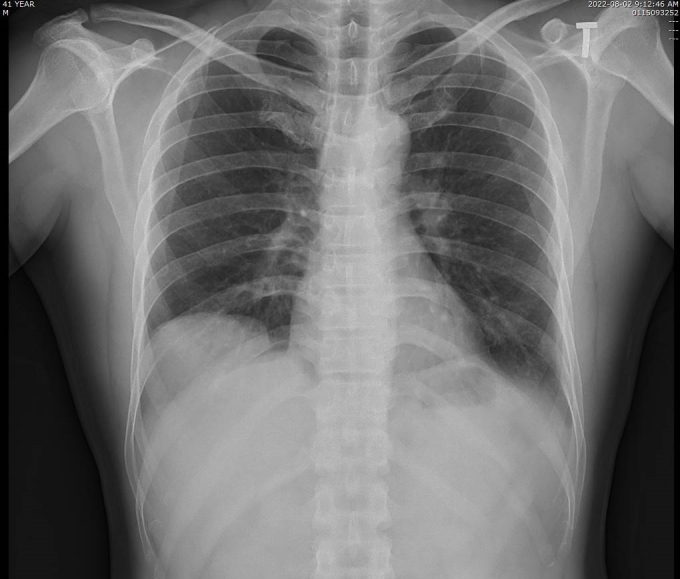

Phát hiện bệnh hiếm sau nhiều ngày ho, khó thở. Một người đàn ông 42 tuổi ở Quảng Nnh ho nhiều, khó thở, cơn đau tăng lên khi nằm ngửa, bác sĩ khám phát hiện bị nhão cơ hoành - một bệnh hiếm gặp.

Kết quả chụp cắt lớp vi tính tại Bệnh viện đa khoa tỉnh Quảng Ninh cho thấy vòm hoành phải của bệnh nhân cao, gan di chuyển lên trên gây xẹp thụ động nhu mô phổi lân cận. Bác sĩ chẩn đoán bệnh nhân bị nhão cơ hoành phải, chỉ định phẫu thuật nội soi tạo hình cơ hoành.

Hình ảnh X-quang phổi của bệnh nhân bị nhão cơ hoành khiến tạng dưới ổ bụng di chuyển lên trên gây xẹp thùy dưới phổi phải. Ảnh: Bệnh viện cung cấp

Cơ hoành là phần cơ hình vòm, ngăn cách giữa khoang ngực có chứa tim, phổi với khoang bụng chứa các cơ quan trong ổ bụng. Cơ hoành là cơ chủ yếu của hệ hô hấp, nâng đỡ và hỗ trợ con người hít thở bình thường trong mọi trạng thái. Khi bị khiếm khuyết, cơ hoành chỉ như một miếng màng mỏng, mất trương lực và không co giãn được. Khi đó các cơ quan trong ổ bụng sẽ dễ dàng đẩy cơ hoành bị nhão lên trên và chèn ép lên phổi khiến người bệnh khó thở.

Bác sĩ cho biết nhão cơ hoành là bệnh lý hiếm gặp, khó phát hiện và dễ bị chẩn đoán nhầm với các bệnh khác, như nang thùy dưới phổi, viêm phổi, bệnh phổi biệt lập... do các triệu chứng không đặc trưng, thường phát hiện tình cờ khi chụp X-quang phổi.

Nhão cơ hoành trái và phải có triệu chứng khác nhau. Nhão cơ hoành phải gây khó thở, đau tức ngực, viêm phổi...; còn nhão cơ hoành trái gây đau vùng mũi ức hay hạ sườn trái, ợ hơi, buồn nôn nhất là sau khi ăn no, rối loạn tiêu hóa.